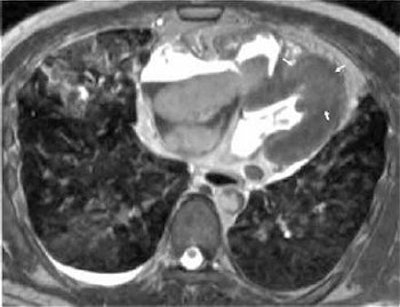

Their patient was a 46-year-old male smoker with no history of cardiac disease. He was found in his home, dead from cardiopulmonary arrest. A whole-body postmortem CT exam was done 30 minutes after death and showed diffuse ground-glass attenuation in both lungs, suggestive of pulmonary edema due to cardiac pump failure, but there was no sign of ischemic myocardium, wrote lead author Dr. Seiji Shiotani, from the department of radiology. Shiotani's co-authors are from the departments of pathology, cardiology, internal medicine, and emergency medicine.

![]() |

| Postmortem CT of the chest shows diffuse ground-glass attenuation in both the right left lower lobes. |

In addition, the heart was of normal size and a pathological examination showed no wavy fibers or edema in the left anterior descending (LAD) coronary artery territory myocardium.

"We reach the conclusion that acute plaque change in the LAD precipitated acute myocardial injury that was potentially reversible but had produced lethal pump failure (cardiogenic shock)," the group wrote (Radiation Medicine, March 2005, Vol. 23:8, pp. 563-565).